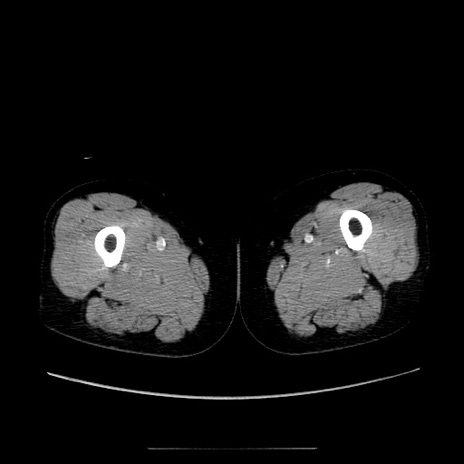

症例5(横断像)

【症例】70歳代女性

【主訴】お腹が張る

【現病歴】1週間くらい前から腹部膨満の自覚あり。昨日夜から増悪したため、本日救急外来受診。

【身体所見】意識清明、BT 36.5℃、BP 165/106mmHg、HR 80bpm、SpO2 98%、腹部:膨満、軟、自発痛・圧痛なし、触診にて不快感あり、腸蠕動音:減弱

【データ】WBC 12600、CRP 1.04